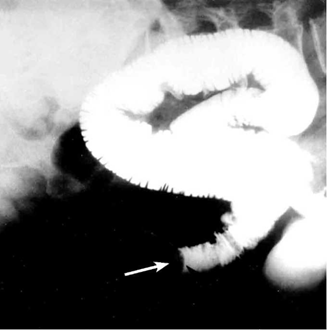

לעתים רחוקות, כדי לקבוע את גובה החסימה ואת מידתה בחולים הלוקים בחסימה דינמית, או כדי להבדיל בין שתי צורות החסימה, יש לצלם את החולה לאחר בליעת חומר ניגוד נספג מסוג גסטרוגרפין. בחסימה דינמית ניתן למצוא התקדמות של חומר הניגוד עד לחסימה (תצלום 6.4), ואילו בחסימה אדינמית ניתן למצוא אמנם מעבר לכל אורך המעי, אך מעבר איטי ביותר. לחולים שבהם יש חשד לחסימת הכרכשת, אין לתת בריום דרך הפה אלא לבצע חוקן בריום תחילה. ב- CT בטן עם חומר ניגוד ניתן לראות לולאות מורחבות שלאחריהן לולאות התמט, בצקת של הלולאות ונוזל ביניהם (תצלום 7.4).

בחולים הלוקים בחסימת מעי על-ידי אבן מרה החודרת למערכת העיכול אפשר להדגים את החסימה בעזרת חומר ניגוד (תצלומים 8.4 ו-9.4) או ב-CT (תצלום 10.4). בחולים הלוקים בחסימת מעי על-ידי פיטובזואר להדגים את החסימה בעזרת חומר ניגוד (תצלום 11.4) או ב-CT. התפשלות של המעי ניתנת להדגמה בצילום בריום או בטומוגרפיה ממוחשבת (CT) (תצלום 12.4 - 13.4)